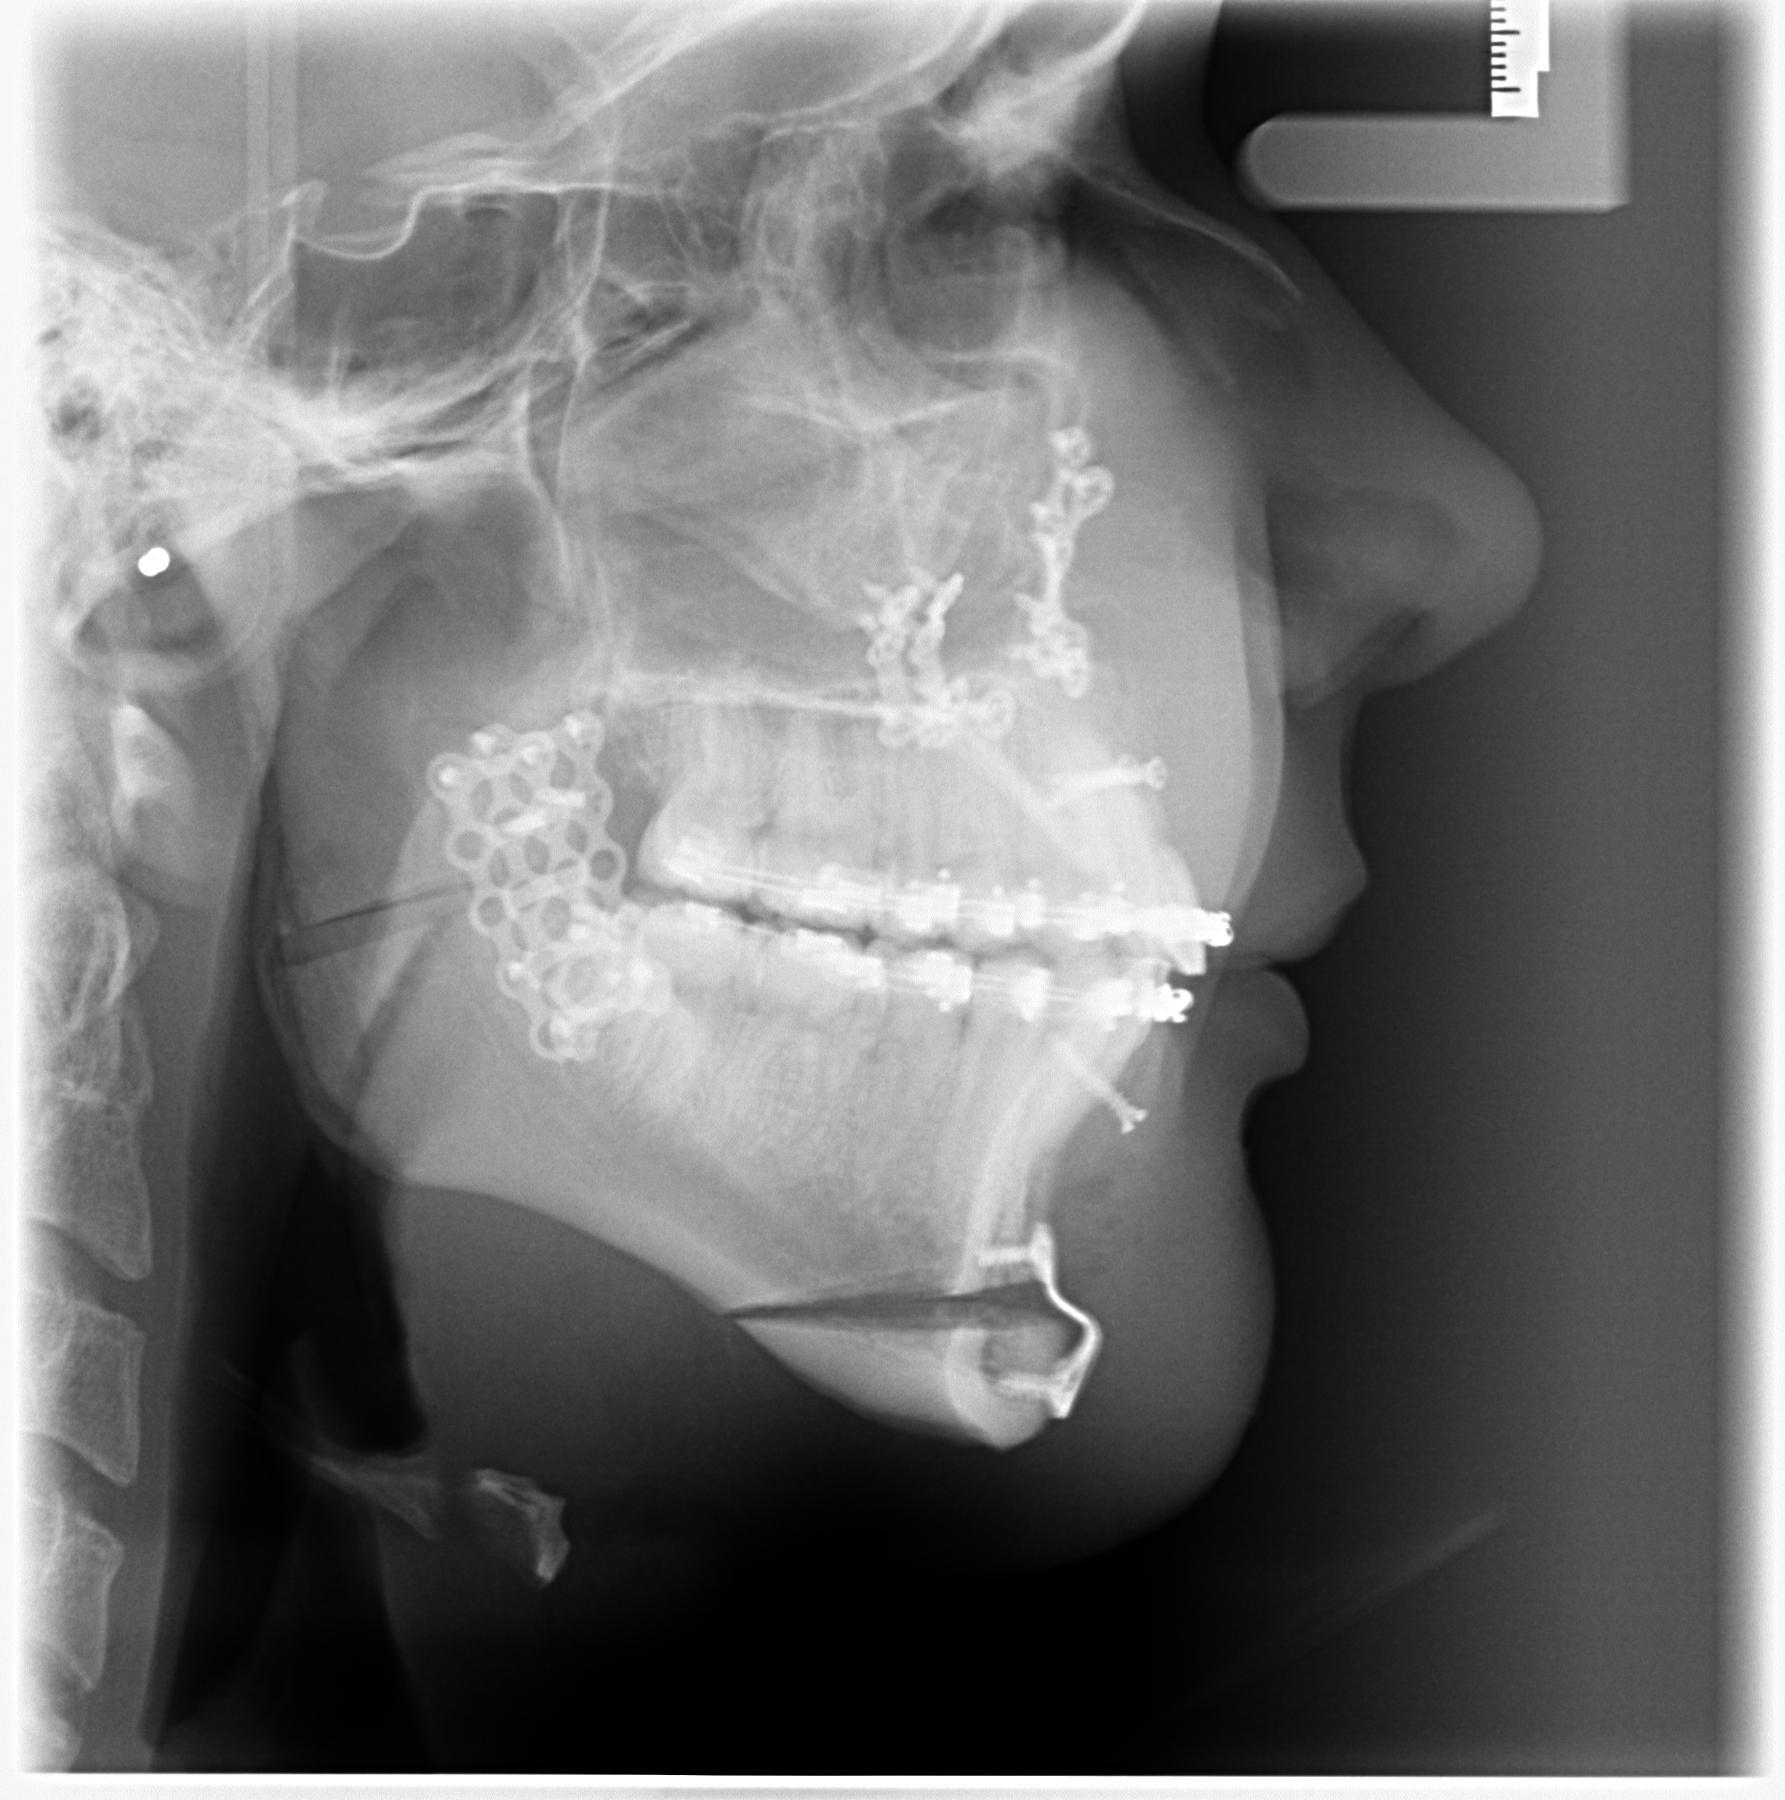

Before

1770743315044

1770743326130